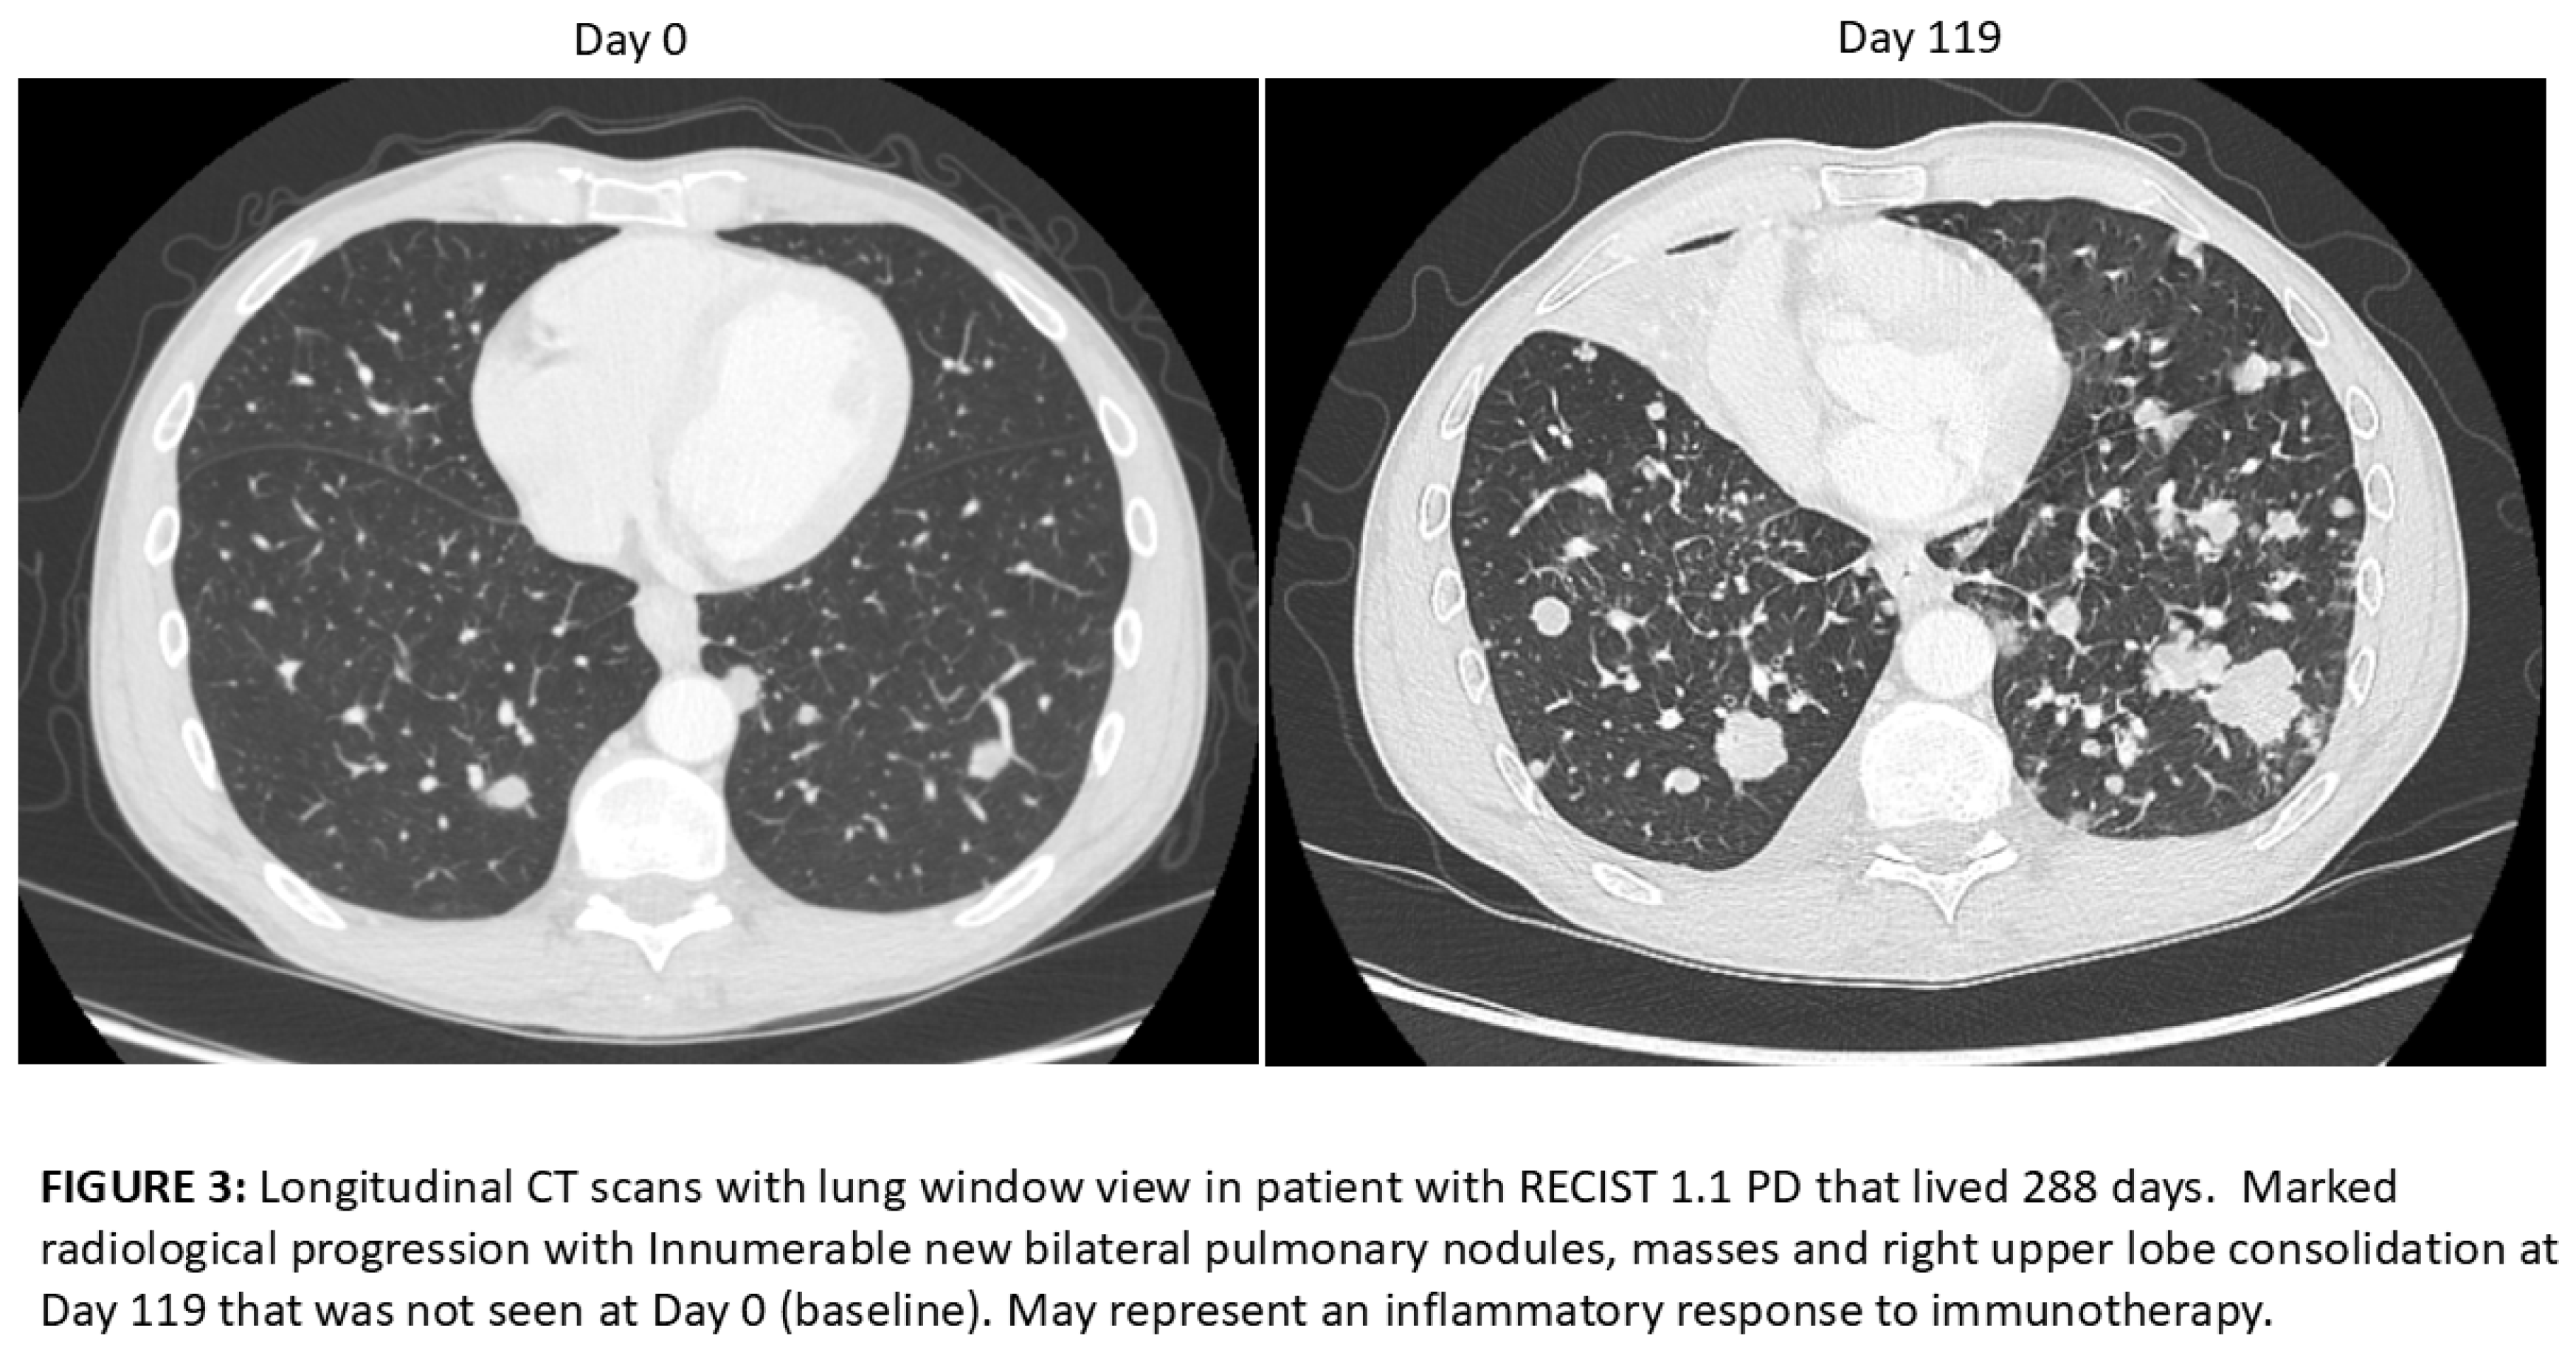

- Wang, Q.; Gao, J.; Wu, X. Pseudoprogression and hyperprogression after checkpoint blockade. International immunopharmacology 2018, 58, 125–135. [Google Scholar] [CrossRef]

- Chiou, V.L.; Burotto, M. Pseudoprogression and Immune-Related Response in Solid Tumors. Journal of clinical oncology : official journal of the American Society of Clinical Oncology 2015, 33, 3541–3543. [Google Scholar] [CrossRef]

- Jia, W.; Gao, Q.; Han, A.; Zhu, H.; Yu, J. The potential mechanism, recognition and clinical significance of tumor pseudoprogression after immunotherapy. Cancer biology & medicine 2019, 16, 655–670. [Google Scholar] [CrossRef]